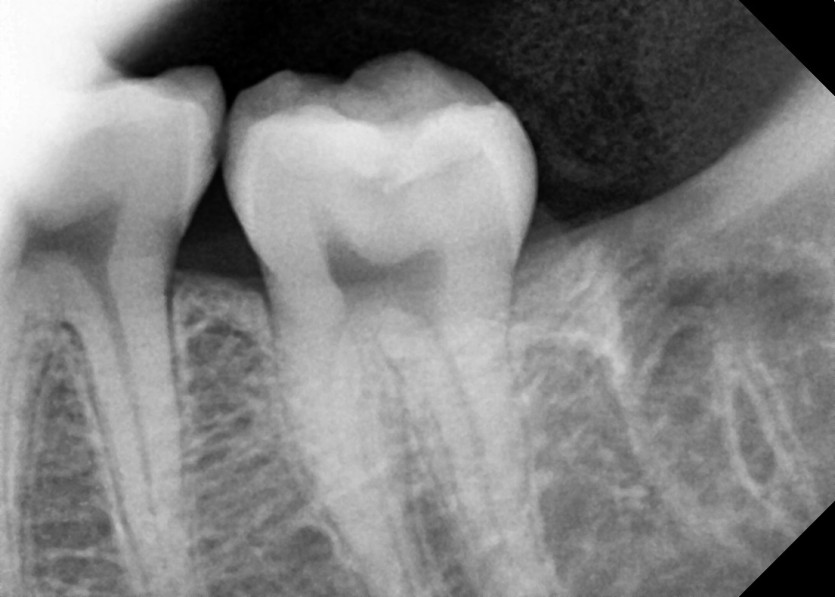

#38,48 사랑니 발치

구강 외과 전문의가 당일 발치했습니다.